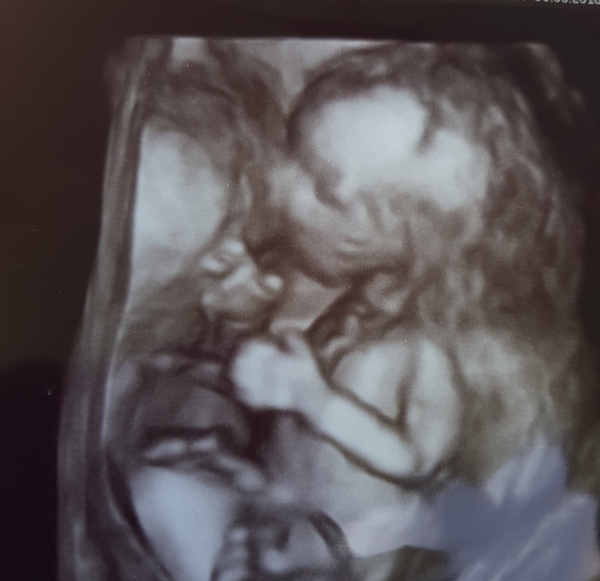

MrsTeaPlease · 30/06/2018 23:09

We are also having another little boy! Found out this morning. I could see before the sonographer even said!